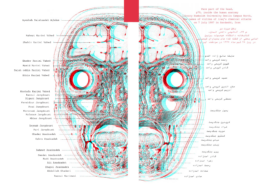

Reports and interviews on huge chemical attack and the genoide by saddam hosein during the iraq-iran war (1980-88)

Reports and interviews on huge chemical attack and the genoide by saddam hosein during the iraq-iran war (1980-88)